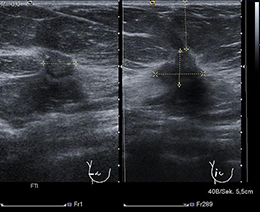

Ist die Ultraschalluntersuchung nicht besser für mich?

Die Ultraschalluntersuchung wird mit einem hochfrequenten speziell für die Brust entwickelten Schallkopf durchgeführt. Die Sonographie ist eine wichtige ergänzende Methode zur Mammographie und wird gezielt eingesetzt zur weiteren Abklärung suspekter Befund und bei sehr dichtem Drüsengewebe. Grundlage der Bildgebung sind hier Ultraschallwellen. Es besteht keine Strahlenbelastung für die Patientin. Allerdings kann die Ultraschalluntersuchung Brustkrebsvorstufen nicht erkennen.